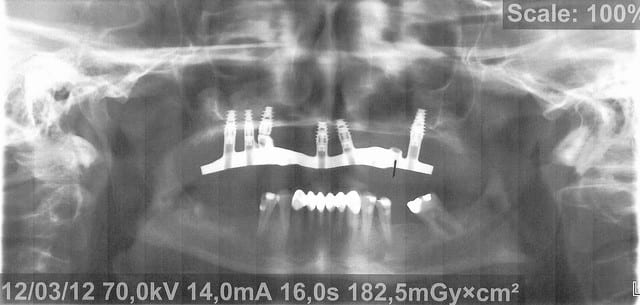

Voici donc les panos pour vos petits yeux ébahis

Profitez bien : elles sont ds l ordre chronologique...

Je vous donne une petite info : le comblement au BioOss a échoué largement...et on lui propose des greffes crâniennes à présent

- On y voit un manque flagrant de densité du greffon

- On y voit une perte d'un implant sans changement de plan de traitement, on se retrouve avec un seul implant du coté où mastique le patient

- On y voit une armature qui baille sur le seul implant qui reste secteur 2, et donc manque de passivité

- On y voit ce qui devait arriver,

Mais je vois aucun rapport entre l’échec et la nature du matériau mis en place dans le sinus....

Mais je persiste et je te dis que la nature du BioOss pose problème ds tous je dis bien tous les sinus lifts et même les autre endroits

Il faut chercher ds son mode de fabrication chez les Suisses hypersécuritaires